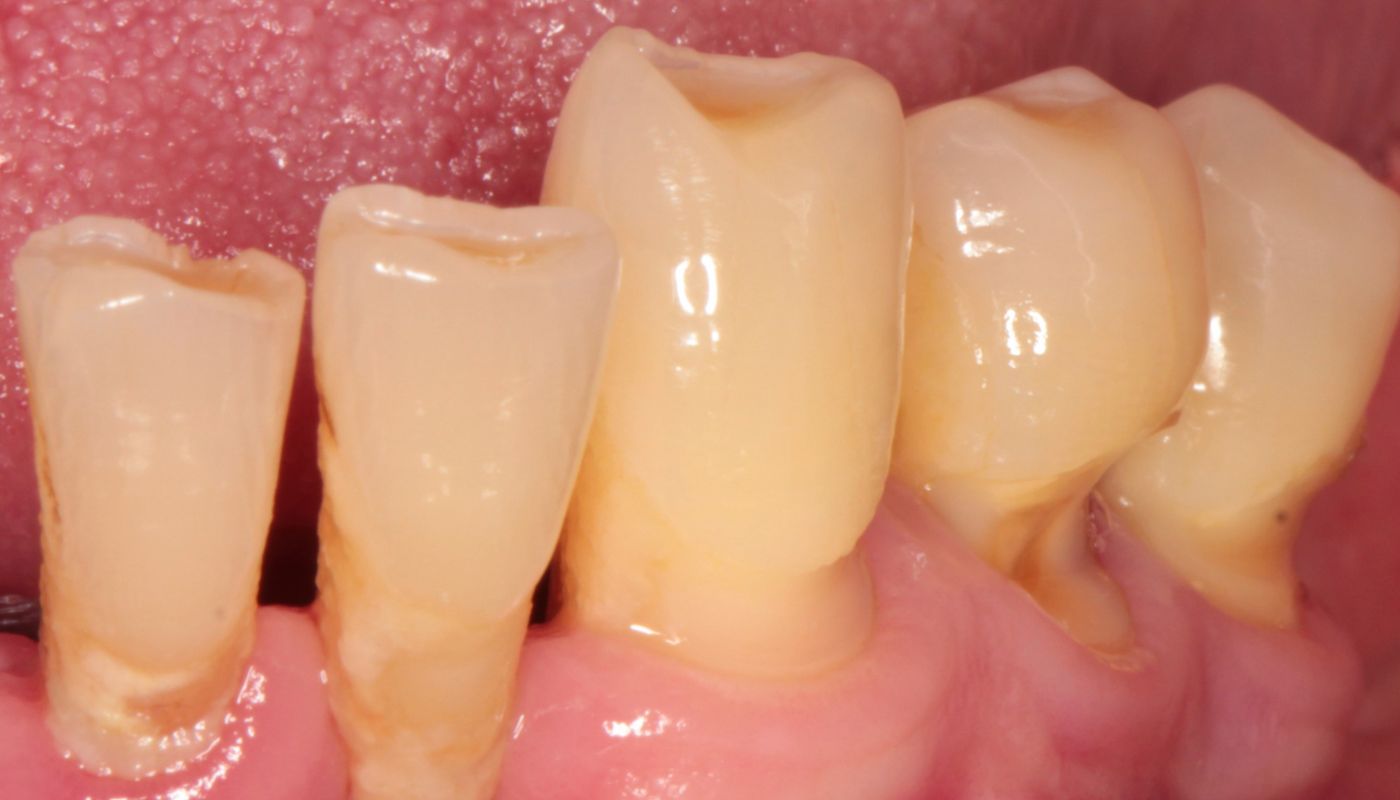

Odsłonięte szyjki zębowe narażone są większą adhezję (przyleganie) płytki nazębnej oraz osadzanie się kamienia. Dodatkowo, w wyniku niekorzystnej akumulacji płytki bakteryjnej oraz różnicy grubości szkliwa przy szyjce zęba w stosunku do korony, dochodzi bardzo często do zmian próchnicowych. Leczenie próchnicy w przypadku odsłoniętych szyjek jest obarczone dodatkowym ryzykiem powikłań (np. konieczność leczeni kanałowego). Wynika to z lokalizacji oraz bliskości miazgi.

Recesja dziąseł, czyli odsłonięte szyjki zębowe mogą pojawiać się z wielu powodów. Należy wyszczególnić recesje spowodowane przez czynniki patologiczne wynikające z namnażających się bakterii oraz recesje o uwarunkowaniach anatomicznych, wynikających z budowy zębów, kości, wady zgryzu oraz cienkiego fenotypu dziąseł.

Odsłonięcie szyjek zębowych, gdzie pojawia się stan zapalny, spowodowane jest nagromadzeniem się płytki bakteryjnej, która doprowadza do powstawania kamienia nazębnego. Nieleczona wiele lat choroba przyzębia, zwana paradontozą (z łac.periodontitis) powoduje trwałe zanikanie dziąseł i kości, a w konsekwencji odsłonięte szyjki oraz powierzchnie korzeni.